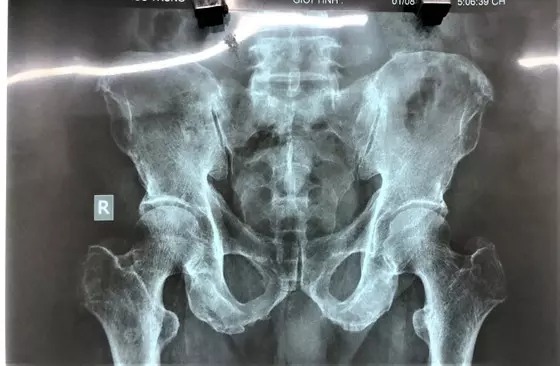

Sáng 2/, TS-BS-CKII Nguyễn Thế Vũ, Phó Giám đốc phụ trách Bệnh viện quận 7 (TPHCM) xác nhận với Sài Gòn Giải Phóng, đơn vị này vừa cấp cứu phẫu thuật thành công cho bệnh nhân T.H.T. (71 tuổi, ngụ quận 4, TPHCM) bị mắc dị vật là trái bí đao dài trên 10cm trong vùng hậu môn trực tràng.

Theo thông tin ban đầu, vào khuya 1/8, ông cụ được người nhà đưa đến nhập viện. Khai thác thông tin cho thấy, bệnh nhân đã tự đưa một trái bí đao vào hậu môn, sau đó trượt tay nên kẹt sâu vào bên trong. Ông cụ đã cố gắng đi vệ sinh, tự dùng tay lấy ra nhưng không được nên đến bệnh viện cấp cứu.

Kết quả chụp X-quang xác định dị vật nằm sâu trong lòng trực tràng. Dị vật là một trái bí đao có kích thước 6x10cm. Các bác sĩ nội soi đã hội chẩn cùng Khoa Ngoại. Sau đó, nội soi trực tràng, nong hậu môn, dùng kẹp có móc, kẹp chặt nhẹ nhàng, xoay vòng và kéo dị vật ra ngoài thành công.

Hiện sức khỏe bệnh nhân đã ổn định và đang được theo dõi. Về nguyên nhân, người này chia sẻ với bác sĩ rằng dùng trái bí để chữa bệnh trĩ.